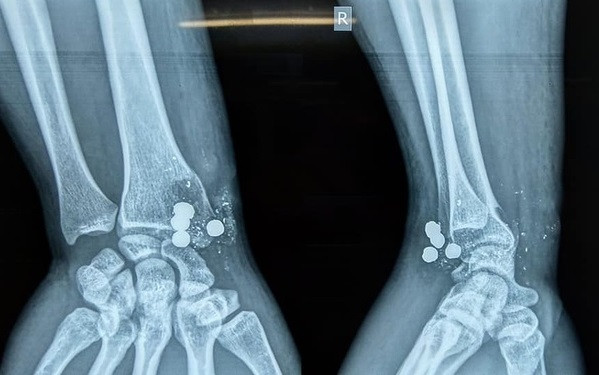

Nghịch súng kíp, nam thanh niên bị 5 viên đạn bắn trúng tay ảnh 1Các mảnh đạn trong cổ tay anh T.

Thăm khám và chụp chiếu tại bệnh viện Đại học Y khoa Vinh, bác sĩ phát hiện anh T. bị vỡ đầu dưới xương quay, tổn thương cung động mạch gan tay sâu, không tổn thương gân gấp duỗi và các dây thần kinh. Trong cổ tay anh T. còn 4 mảnh bạn lớn bằng chì và nhiều mảnh kim loại nhỏ khác. Một viên lớn đã xuyên từ trước ra sau.